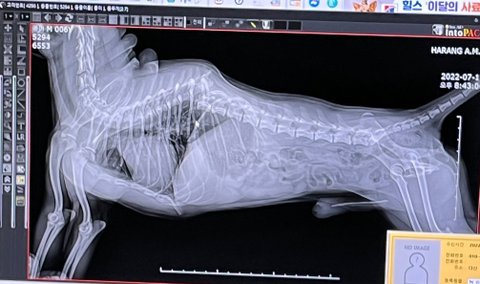

반려견 교통사고 척추 골절..

7월 11일 남양주시 금곡동에서 아버지와 저희 집 강아지가 산책을 하다가 강아지가 차에 치이는 사고를 당했습니다.

목줄 착용하고 있었고, 강아지는 아버지 뒤쪽에 있었던 상황이였습니다. '깨갱'하는 소리가 나서 아버지가 뒤를 돌아보았는데 자동차는 그냥 지나갔고 강아지는 척추가 부러졌습니다.

완전히 어그러졌어요........

동생을 급히 불러서 24시 동물 병원에 갔는데 수술을 해도 하반신 마비에 대소변을 못 가릴 것이라는 이야기를 들었고 우회적으로 안락사 이야기를 꺼내길래 저희 가족은  밤새 울면서 고민하고 또 고민하였습니다. 일단 수술은 하기로 하였지만 수술비만 600... 입원비에 치료비까지 하면 1,000만 원은 우습게 나올텐데...